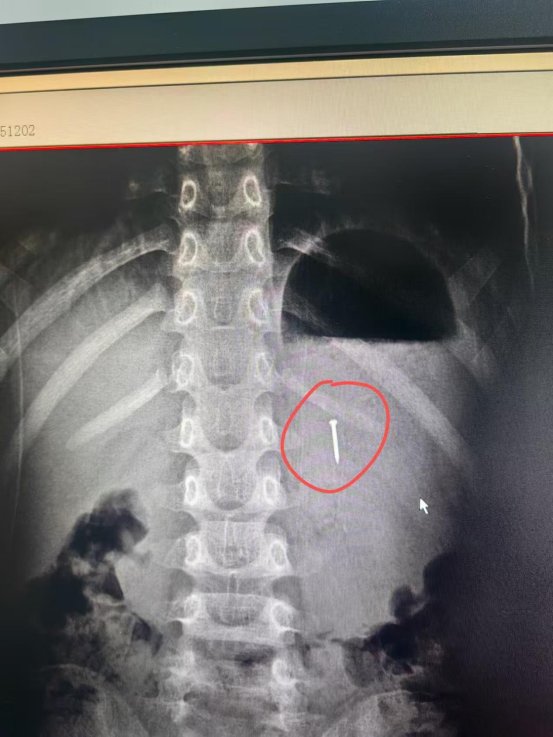

随后,患儿被推进手术室。麻醉科医生轻柔实施静脉麻醉,患儿很快进入镇静状态。消化内科医生在胃内找到约 1厘米长的工字钉 —— 此时钉尖已贴胃壁,再晚恐穿透。内镜护士递上专用异物钳,主任精准夹住钉尾,数分钟内便将工字钉完整取出,全程无出血、无黏膜损伤。